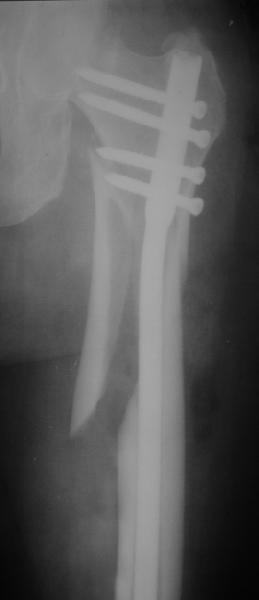

При межвертельных переломах с цефаломедуллярными гвоздями бывает, что проксимальый винт проходит или черед периферический отломок, или прямо над ним. И если остался диастаз, то этот винт при осевой нагрузке не дает сблизиться отломкам. Пример такого остеосинтеза в застарелом случае в приложении.

В качестве предупреждающей меры можно долотом разрушить латеральную стенку дистального отломка под винтом.